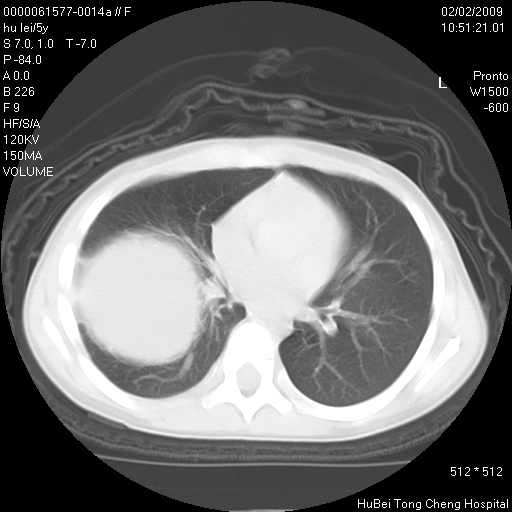

标题: PED1732:M5Y,右肺囊性占位!

患者:男,5。无明显不适,拍胸片考虑右肺囊肿。

行ct扫描,图象如下:

考虑先天性巨大支气管肺囊肿,建议包虫实验除外肺包虫。

考虑先天性巨大支气管肺囊肿

右肺巨大囊性占位性病变;考虑巨大肺囊肿,不排除淋巴管瘤可能。